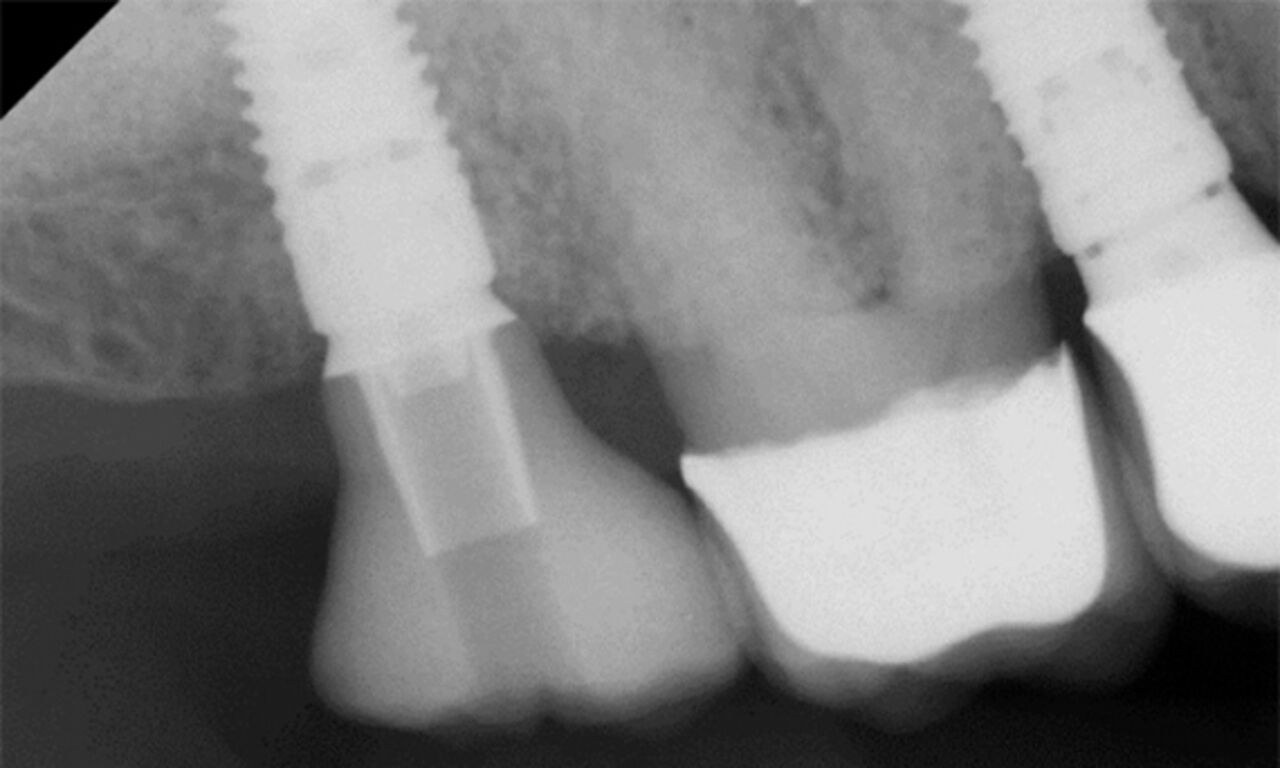

Langfristiger Knochenerhalt

Lassen Sie sich von unserer Erfolgsbilanz inspirieren: Wir haben den Standard in puncto Knochenerhalt gesetzt. Aufbauend auf dem bewährten Renommee des Astra Tech Imlant Systems für eine schnelle, vorhersagbare Osseointegration. Die OsseoSpeed-Oberfläche beitet langfristigen Knochenerhalt und übertrifft zwei andere Implantat-Oberflächen in Bezug auf marginalen Knochenerhalt in 1-Jahres- und 5-Jahres-Follow-ups.*

* Norton MR et al. Int. J. Oral Maxillofacial Implants 2020; 35 (6): 1099 - 1111